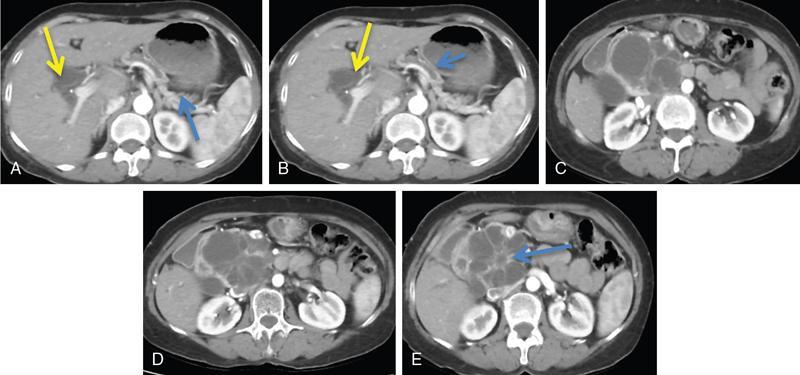

Ritu K. Kashikar, Shrinivas B. Desai, Pooja Punjani Vyas, Nilesh Doctor, Vivek Shetty Advancement and extensive use of imaging in recent times has to lead to increased detection and recognition of cystic pancreatic masses. Imaging however, plays a vital role in noninvasive diagnosis of these lesions, avoiding unnecessary intervention and planning management and follow up guidelines. The aetiology of pancreatic cysts ranges from primary cystic neoplasm to cystic degeneration of solid neoplasm to nonneoplastic cysts (Table 9.19.1). Cystic tumours of the pancreas comprise around 10%–15% of cystic lesions of the pancreas. The aim of this chapter is to educate the reader regarding imaging features of cystic lesions of pancreas, how to differentiate between cysts which can be left alone and those that require further management and also emphasize on latest international guidelines used in stratification of these lesions. Cystic pancreatic lesions are often incidentally detected on USG abdomen performed for other reasons. Although USG is an excellent modality for evaluation of cystic lesions elsewhere, it is unable to adequately characterize pancreatic cysts due to retroperitoneal location of the organ and other confounding factors such as obesity and gases. Most lesions detected on USG require characterization with either MDCT or MRI with MRCP. CEUS improves accuracy in the differentiation between a solid and a cystic lesion and also in determining whether enhancing septa or nodules are present within the cystic lesion. Currently USG also does not have a role in follow up algorithms of pancreatic cystic lesions. Multidetector CT evaluation of pancreatic lesions is best performed with a multiphasic technique (Table 9.19.2). The phases include a precontrast scan, an early arterial angiographic phase, a pancreatic parenchymal phase, and a portal venous phase. The precontrast scan is important for detection of calcification, which may be diagnostic of some lesions. Mucinous cystic neoplasms may be hyperdense on nonenhanced scan suggesting mucin content or haemorrhage. The arterial phase aids in detection of hyperenhancement neovascularity and arterial involvement in pancreatic masses. Optimal parenchymal enhancement of the pancreas is achieved at 35–45 seconds after initiation of injection of contrast agent. This is the pancreatic parenchymal phase. It is in this phase that the tumour pancreas contrast is maximum (Fig. 9.19.1, Table 9.19.3). Most hypoenhancing pancreatic lesions are best detected in this phase. The portal venous phase allows in detection of venous involvement and hepatic metastasis. Delayed phase is typically not required in cystic masses. MDCT has an accuracy of 56%–85% for characterization of cystic pancreatic lesions. MR imaging affords the best noninvasive means for the evaluation of cystic lesions of the pancreas due to superior soft tissue resolution. The helpful distinguishing characteristics of cystic pancreatic lesions, morphology of septae, relation to pancreatic duct are easier to detect at MR imaging and MR cholangiopancreatography (MRCP) than at CT (Table 9.19.4). Studies however indicate that MDCT and MRI are comparable in identifying malignant behaviour of cystic pancreatic lesions. The MRI protocol for evaluation of cystic lesions of pancreas includes T2-weighted single-shot fast spin-echo, T1-weighted in-phase and opposed-phase gradient echo, diffusion-weighted imaging, T2-weighted fat-suppressed fast spin-echo. Three-dimensional T1-weighted fat-suppressed spoiled gradient-echo T2-weighted MRCP. Postcontrast protocol includes dynamic three-dimensional T1-weighted fat-suppressed spoiled gradient-echo (in arterial, pancreatic and portal venous phases) (Fig. 9.19.2, Table 9.19.3). DWI has not found much utility in cystic neoplasms owing to overlap in ADC values. Some studies suggest role in distinguishing malignant from benign tumours in the case of mucinous cystadenoma and IPMN. Secretin is a peptide hormone produced in the intestinal mucosa, which stimulates the secretion of bicarbonate-rich fluid into the pancreatic ducts and transiently increases the tone of the sphincter of Oddi. The increased fluid distention of the pancreatic duct allows better study of ductal anatomy and identifying communication of pancreatic cystic lesions with the pancreatic duct. EUS is excellent in characterization of cystic lesions of pancreas. The proximity between the transducer and the lesions allows precise definition of the structural component of the cysts and components such as small mural nodules are better visualized with EUS than with other modalities. The other advantage of EUS is that cysts fluid aspiration and cytology can be performed. Tumour markers, genetic markers can be evaluated in the aspirated fluid. This allows comprehensive evaluation of cystic lesion. EUS also has therapeutic advantages allowing endoscopic draining of pseudocysts. Recently endoscopic ablation of cysts has been performed. These advantages have led to increasing use of EUS in recent years. This modality is however not indicated in all lesions and imaging should be able to stratify lesions requiring further invasive investigations. Studies have found PET CT comparable to PET alone or CT to determine presence of malignancy in cystic lesions. False positive findings may however be problematic. There is however no consensus for routinely using PET CT in characterization of cystic pancreatic masses. Serum CA19-9 and CEA are routinely done in all pancreatic masses. Though role in cystic lesions is still controversial. Serous cystadenoma is a benign neoplasm composed of glycogen-rich epithelial cells that form innumerable small thin-walled cysts containing serous fluid. It is the prototype microcystic pancreatic neoplasm. They occur frequently in older women (median age, 65 years) and is also called as grandmother lesion. Approximately 40% of pancreatic serous cystadenoma arise from the pancreatic head and uncinate process and 60% arise from the pancreatic body and tail. Serous cystadenomas are usually discovered incidentally at imaging; however, those that are large may cause symptoms. Patients may present with abdominal pain, palpable mass, anorexia, fatigue/malaise, or weight loss. Rarely the patient may present with jaundice. Genetic alterations similar to those in VHL are seen in sporadic SCA and include tumour suppressor gene VHL mutations and overexpression of vascular endothelial growth factor (VEGF). Allelic loss in chromosome 3 have seen in up to 40% cases of sporadic SCA. Serous cystadenomas are variable in size. The size ranges from <0.1 to 25 cm. The tumours are grossly well demarcated from the surrounding parenchyma. The gross appearance of the lesions is variable. It could be microcystic, consisting of innumerable small cysts giving the macroscopic appearance of a sponge or honeycomb. The presence of multiple, microscopic SCN is characteristic of von Hippel–Lindau (VHL). This variety show a centrally located area of fibrotic scar. In Macrocystic/oligocystic variant, borders with the surrounding parenchyma are less defined and the cystic lesion generally does not exhibit a central scar. The Solid variant, the lack of cystic spaces on gross inspection often gives the initial impression of a neuroendocrine or solid pseudopapillary neoplasm. Serous cystadenomas show nonviscous, clear-to-yellow cyst fluid, which provides an important clue to the distinction of SN from mucinous neoplasms. In contrast to intraductal papillary mucinous neoplasm, there is no connection with main or branch pancreatic ducts. These are clinically benign pancreatic epithelial neoplasms exhibiting serous morphology, characterized by a monotonous, cuboidal epithelial cell proliferation with marked cytoplasmic clearing due to intracellular glycogen. The centrally located epithelial cell nuclei are uniformly round to ovoid and not particularly large or hyperchromatic. Abundant diastase-sensitive cytoplasmic glycogen is highlighted by a periodic acid–Schiff stain. These lesions do not show evidence of necrosis, infiltrative architecture, or lymphovascular/perineural invasion, and mitotic figures are generally not observed. A variably prominent pseudocapsule of fibrosis divides parenchyma from the neoplasm On USG the microcystic variant shows lobulated contour with multiple tiny anechoic cysts separated by septae. the central scar containing calcification can be seen if present. Extremely microcystic, honeycomb variant may resemble a solid lesion at conventional US. The macrocystic type, can be mixed type with multiple large (>20 mm) and small cysts, and the unilocular type, which is more difficult to differentiate from mucinous cystadenoma (MCA). Enhancement of the intralesional sepatations is seen on contrast-enhanced USG allowing better characterization of the lesion. The central scar can show homogenous enhancement. Honeycomb variety appears as a hypervascular lesion owing to its extremely microcystic morphology and may resemble solid masses like neuroendocrine tumours. Pancreatic serous cystadenoma can have a varied appearance on CT depending on the morphologic patterns. Serous cystadenomas are typically solitary but may be multiple in von Hippel–Lindau disease, causing an appearance of disseminated involvement (Table 9.19.5). As mentioned previously, the polycystic pattern is the most common appearance of serous cystadenoma. A pattern of a bosselated collection of cysts that usually number more than six is seen. Each cyst may range from a few millimetres to 2 cm in size (Fig. 9.19.5). The other classic CT features include a lobulated contour and presence of a central stellate scar with calcification. This scar is seen in 30% cases and when present is strongly suggestive of the diagnosis. The intralesional fibrous septae show early enhancement after contrast administration. This is a distinguishing feature, as serous cystadenoma is the only hypervascular lesion among the cystic pancreatic neoplasms. Tiny cysts mimicking a honeycomb are the hallmark of this variant and may be poorly depicted as individual cysts on CT. On unenhanced CT, the honeycomb pattern may appear as a well-marginated lesion with soft tissue or mixed attenuation, depending on the size of the cysts and the amount of fibrous tissue. Moderate to strong enhancement is seen in these lesions (Fig. 9.19.6). This appears as a unilocular cyst or it may contain fewer large (>2 cm) cysts. Imaging Features include a lobulated contour, lack of a prominent thickened peripheral wall, and location in the head of the pancreas (Fig. 9.19.7). Owing to its supreme soft tissue resolution, MRI is the modality of choice in diagnosis of serous cystadenomas. The classic MRI features of microcystic variant includes a lobulated lesion with multiple small T2 hyperintense and T1 hypointense cysts with intervening hypointense fibrous sepate. These lesions do not communicate with the pancreatic duct; hence no dilatation is usually seen. Dilatation of pancreatic duct has however been reported in larger lesions. After the administration of gadolinium, the hypervascularization of the central scar and of internal septa may be seen. The morphology of the honeycomb pattern may also be better depicted on MRI. Multiple tiny T2 hyperintense cysts with intervening hypointense septae are seen (Fig. 9.19.8). The oligocystic variant shows fewer larger T2 hyperintense and T1 hypointense cysts and can mimic mucinous cystadenoma. However, the lobulated contour, together with the absence of wall enhancement and a wall thickness less than 2 mm, suggest the correct diagnosis (Fig. 9.19.9) (Table 9.19.6). The differential diagnosis of serous cystadenoma depends on the variety and are listed in Tables 9.19.7 and 9.19.8. Lesions with classic imaging features do not require further investigation or fluid analysis. The fluid in classic cystadenomas is yellow in colour and does not show elevated amylase, mucin or tumour markers. Approximately 20%–50% cases show cytological positivity for periodic acid-Schiff and cytokeratin AE1 and 3. Hemosiderin laden macrophages also do not have high diagnostic accuracy and are seen in only about 43% cases. Current management guidelines suggest (Table 9.19.9). Resection involves distal pancreatectomy or Whipples, depending on location of the tumours and is currently reserved for truly symptomatic cases. Mucinous cystic tumours are a rare subset of cystic neoplasms, constituting approximately 2.5% of pancreatic exocrine tumours. TABLE 9.19.10 The defining and characteristic histopathologic feature of mucinous cystic neoplasms (MCNs) is the presence of ovarian-type stroma similar to that observed in biliary cystadenomas. International Association of Pancreatology recommend that all suspected MCNs be surgically resected. A significant female predilection is seen with approximately 99.7% cases seen in women. As opposed to serous cystadenomas these lesions occur in middle aged women and hence the term mother lesions is used to describe these. The approximate age of occurrence is 50 years with a range from 20–82 years. Mucinous cystic tumours are a dominant cyst that is round or oval and is encapsulated. MCNs may grow slowly over time, at an average rate of 4 mm per year. The most common locations are the pancreatic body and tail (up to 75%). Stromal elements similar to ovarian stroma are the hallmark and key feature that aids in differentiation from IPMN, whose stromal elements are ductal in origin. Tall columnar cells with intracellular mucin arranged in a single row or vertically, forming papillary or polypoidal projections, constitute the epithelial elements. Portions of benign appearing epithelium can be seen adjacent to areas of invasive carcinoma in the same tumour. These lesions show smooth contour on gross appearance with few internal sepate. Peripheral calcification, mural nodule if present suggest malignant cyst (Fig. 9.19.11, Table 9.19.11). Lesions may be asymptomatic in 25% cases. Patients my present with pain in abdomen. Mucinous cystadenoma can also present with pancreatitis. Considering most lesions are located in distal body and tail involvement of splenic vein may lead to left sided portal hypertension. Mucinous cystic tumour is a well-circumscribed cystic mass in the pancreas. Lesions can have an irregular contour to the wall, septations, mural nodularity, and peripheral calcifications. The lesion may however be echogenic due to high by mucin content or haemorrhage which may impair the detection of other features. CEUS may improve detection rate of septa and mural nodules. Lesions are typically well-circumscribed with smooth contour. On unenhanced CT, mucinous cystadenoma may appear hypodense or slightly hyperdense content, due to the presence of variable amount of mucin and haemorrhage. Curvilinear calcifications occur along the periphery of the lesion and are seen in 15% of cases, in contrast study enhancement of the fibrous cyst wall along with enhancement of any septations or mural nodules is seen (Figs. 9.19.12 and 9.19.13).